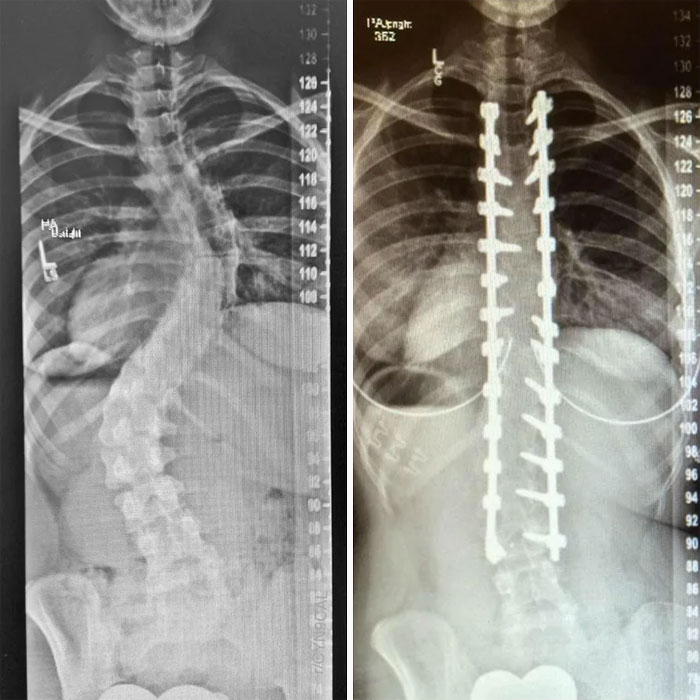

X-Rays Of My Spinal Fusion Surgery Before And After